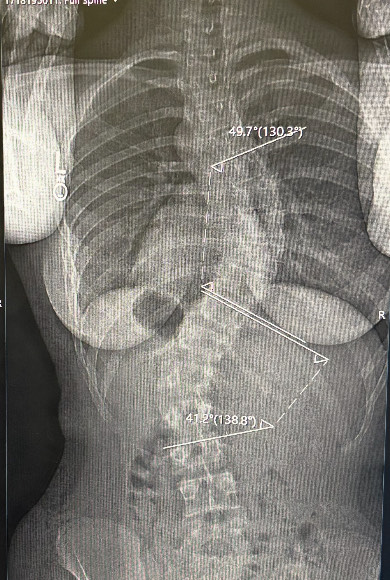

I can’t help but feel responsible for that. I know she took a risk, but at the same time, I understood how hard it was to stay committed to something so uncomfortable, having been through the same struggle. Maybe I should have pushed her more, but I also didn’t want to push her too hard, knowing how hard it was for me. Now, surgery is an option. Thankfully, it’s not mandatory, but her scoliosis is more severe than mine, and I can’t help but worry. I want to help her make the best decision, one that’s right for her.